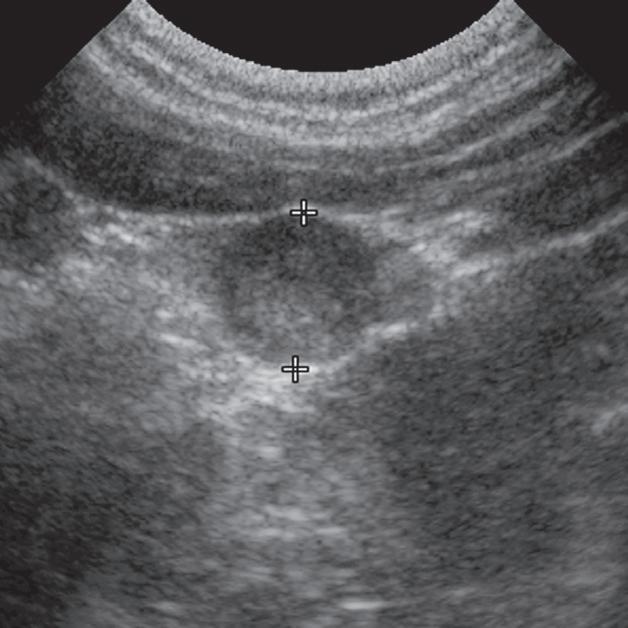

Badanie wykonano u 12-letniej, kastrowanej samicy labradora retrievera z wcześniej zdiagnozowanymi masami płucnymi i szyjnymi. W badaniu USG uwidoczniono kulisty, hipoechogeniczny guzek w obrębie prawego płata tarczycy (a). W TK masa jest nieznacznie hipodensyjna w obrazach bez wzmocnienia (b – strzałka). Lewy płat tarczycy ma prawidłową wielkość i jest hiperdensyjny (b – grot strzałki). Masa ulega umiarkowanemu wzmocnieniu po podaniu środka kontrastowego, jednak w mniejszym stopniu niż sąsiedni prawidłowy miąższ tarczycy (c – strzałka) i jej przeciwległy płat. W obrazach w rekonstrukcji grzbietowej w projekcji MIP po podaniu środka kontrastowego uwidoczniono przebieg obu tętnic szyjnych wspólnych dogrzbietowo względem płatów tarczycy (d – groty strzałek). Cieńszy przekrój MIP wykluczający tętnice szyjne ukazuje płaty tarczycy (e – strzałki) oraz lokalizację masy w obrębie prawego płata (e – grot strzałki). Biopsja wycinkowa wykazała raka tarczycy o utkaniu litym i pęcherzykowym z naciekaniem naczyń i torebki

Badanie wykonano u 12-letniej, kastrowanej samicy owczarka australijskiego z prawostronną masą w dobrzusznej części szyi. Badanie USG wykazało dużą, litą, unaczynioną masę w obrębie prawego płata tarczycy (a) oraz mniejszą, hipoechogeniczną masę w obrębie lewego płata (b). Obrazy TK przed i po podaniu środka kontrastowego (c–f) ułożone od doczaszkowych do doogonowych ukazują dużą, prawostronną, jednorodnie wzmacniającą się masę (c–f – duża strzałka) z niewyraźną granicą dobrzuszną oraz pozatorebkowym szerzeniem się i rozlanym wzmocnieniem pokontrastowym przyległych tkanek (e, f – grot strzałki). W obrazie bardziej doczaszkowym widoczny jest prawidłowy lewy płat (c, e – mała strzałka), natomiast w obrazie bardziej doogonowym jest on powiększony i ma niższą gęstość, niż można by oczekiwać, co sugeruje obecność drugiej, mniejszej masy (d, f – mała strzałka). W obrazach reformowanych wzdłuż osi długiej widać dwa małe guzki w lewym płacie (h – małe strzałki). Wyniki obrazowe potwierdzono podczas zabiegu (i, j – strzałki). Biopsja wycinkowa wykazała prawostronnego raka tarczycy z naciekaniem pozatorebkowym oraz lewostronnego gruczolaka tarczycy